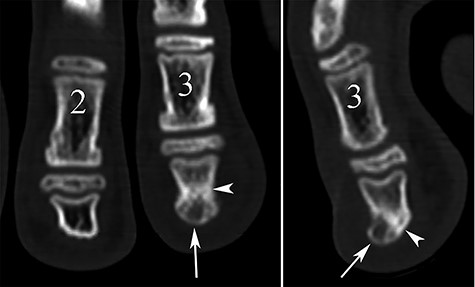

Conventional radiography showed a discrete deformation and irregular density of the phalangeal tuft (Fig. 2). The color Doppler ultrasound showed a hypervascularized pattern of swollen soft tissues on the dorsal aspect of the phalangeal tuft, suggesting a glomus tumor (Fig. 3). A CT scan showed a small lucent bone area within a focal hypertrophy of the phalangeal tuft with adjacent bone sclerosis (Fig. 4). Based on this latest examination, the diagnosis of OO of the distal phalanx was proposed as diagnosis.

CT reconstruction images showing a small central lucent bone area in the phalangeal tuft on the coronal plane (arrow in A) and a focal dorsal prominence of the tuft with lucent content (arrow) on the sagittal view (B). Note also the sclerosis of adjacent bone (arrowheads).